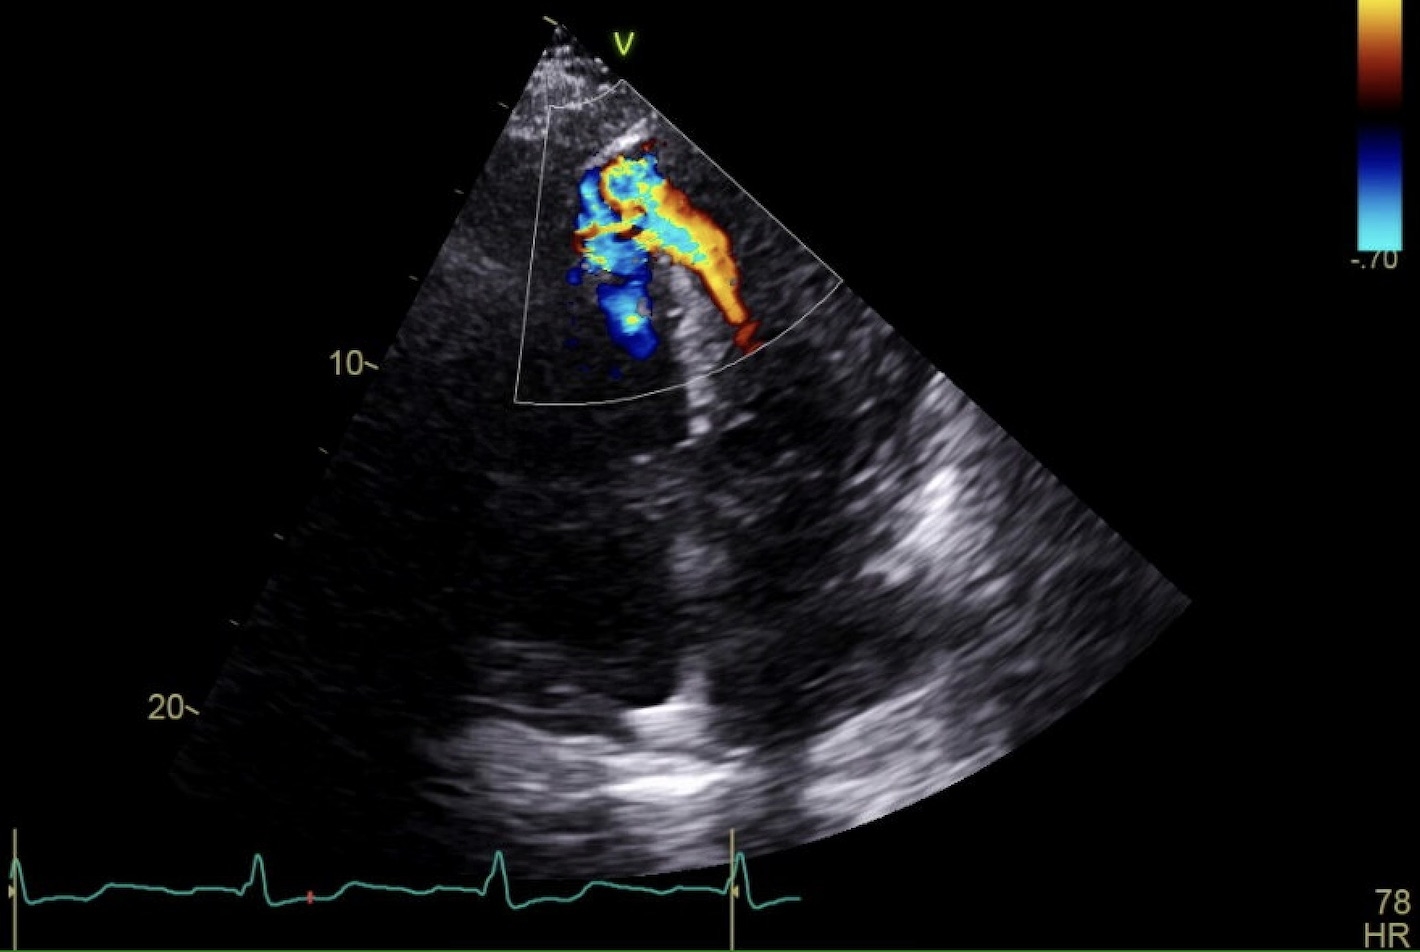

A 73-year-old male with hypertension and hyperlipidemia presented with four weeks of progressive dyspnea. He was diagnosed with an anterior STEMI and underwent left heart catheterization, receiving four stents—three in the LAD and one in D1. Despite intervention, symptoms persisted. Transthoracic echocardiogram (TTE) revealed a 1.2 cm ventricular septal defect (VSD) with left-to-right shunt and EF of 76%. Right heart catheterization showed elevated pressures: RA 18 mmHg, RV 56/20 mmHg (mean 40), PCWP 25 mmHg, and cardiac index 4.8. LAD stents were patent. Cardiothoracic surgery recommended delayed VSD repair in one month. One-week post-discharge, the patient returned with two days of worsening dyspnea and tachycardia. Exam revealed a harsh 4/6 holosystolic murmur at the lower left sternal border and bilateral leg edema. Repeat TTE showed VSD enlargement to 1.8 cm with a peak gradient of 34 mmHg and continued shunting. Inpatient VSD repair was planned. Medical management included diuresis with furosemide and afterload reduction using hydralazine and isosorbide dinitrate, titrated to blood pressure. One week later, he underwent successful VSD closure with Cardiocel patch and balloon pump support, which was subsequently removed. He was weaned to room air and discharged with outpatient follow-up.